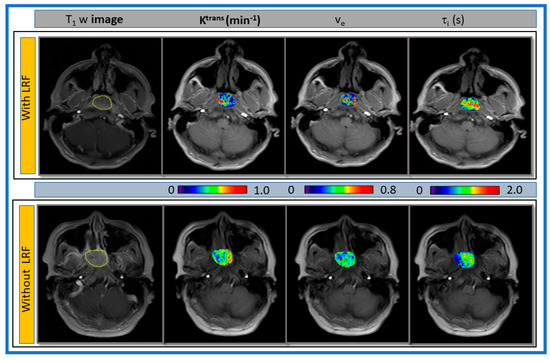

Representative pre-TX T1w MR images of a late phase dynamic series with ROIs and parametric maps of primary tumors Ktrans, ve, and τi overlaid on T1w MR images for a patient with and without LRF of NPC are displayed in Figure 5.

Figure 5.

Representative pre-treatment (TX) T1w images from a late phase dynamic series from patients with (67-year-old female) and without locoregional failure (LRF) (55-year-old male) of nasopharyngeal cancer. Primary tumor parametric maps of volume transfer constant (Ktrans), extravascular extracellular space volume fraction (ve), and mean lifetime of intracellular water protons (τi) overlaid on pre-TX T1w images.